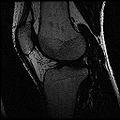

The aim of this project is to develop a methodology for rapid segmentation of knee structures from magnetic resonance (MR) images for subject-specific modeling. The overall goal can be broken down into two specific objectives -

Objective 1: We have adopted a multi-contrast MR methodology to segment knee bones and cartilage structures. The algorithm utilizes tissue intensity information from multiple MR contrasts to segment structures of interest. Inputs to the algorithm included n registered MR image sets. The algorithm created an n-dimensional space of voxel intensities associated with the n image sets. The user assigned seed points to the structures of interest, and the algorithm created a cluster center for each structure of interest. Cluster radii were calculated based on standard deviations obtained from seed points, and tissue structures were classified as label maps.

• Generated label maps of knee and hip structures.